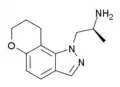

A number of related compounds are known, with a similar structure but having the indole core flipped and/or replaced with related cores such as indoline, indazole, benzothiophene, or benzofuran. These similarly are primarily active as agonists at the 5-HT2 family of serotonin receptors, with applications in the treatment of glaucoma, cluster headaches or as anorectics.

Example 1 [28] | 1-(3-methyl-8,9-dihydropyrano[2,3-g]indol-1(7H)-yl)propan-2-amine | |

|